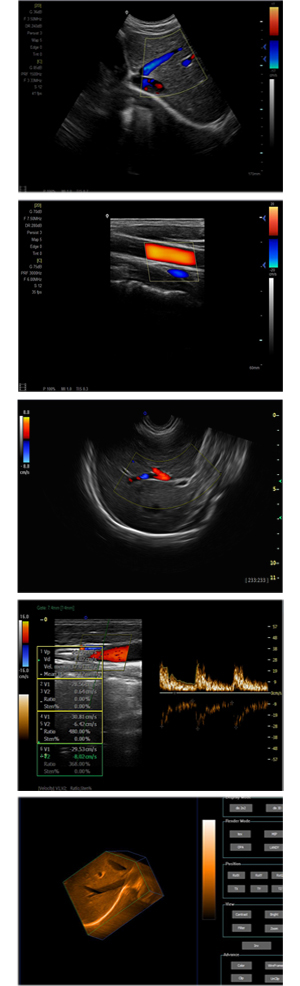

為高集成數(shù)字式彩色多普勒系列產(chǎn)品之一,廣泛實(shí)施于腹部,產(chǎn)科,婦科,血管,小器官,泌尿,新生兒和兒科等臨床,屬全身應(yīng)用型彩色多普勒儀器。

●全身應(yīng)用型包含2D/CFM/PDI/PW/ M等掃描模式;

●升級(jí)版可選配3D、反向諧波等高級(jí)功能。